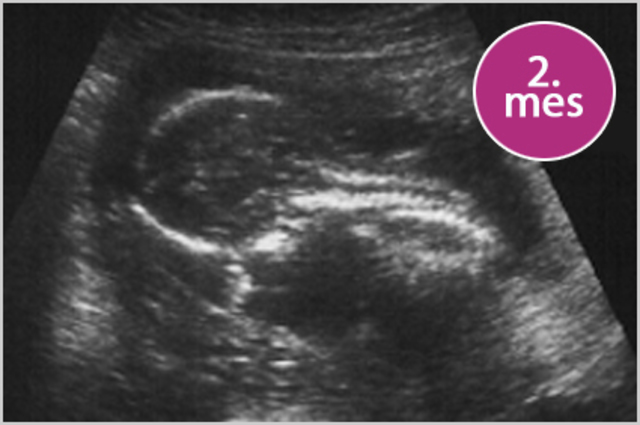

• 8 semanas , 2do mes

8 semanas , 2do mes

mide 3cm, la cara adquiere aspecto humano, se pueden ver los ojos, nariz, boca, los dedos estan bien formados